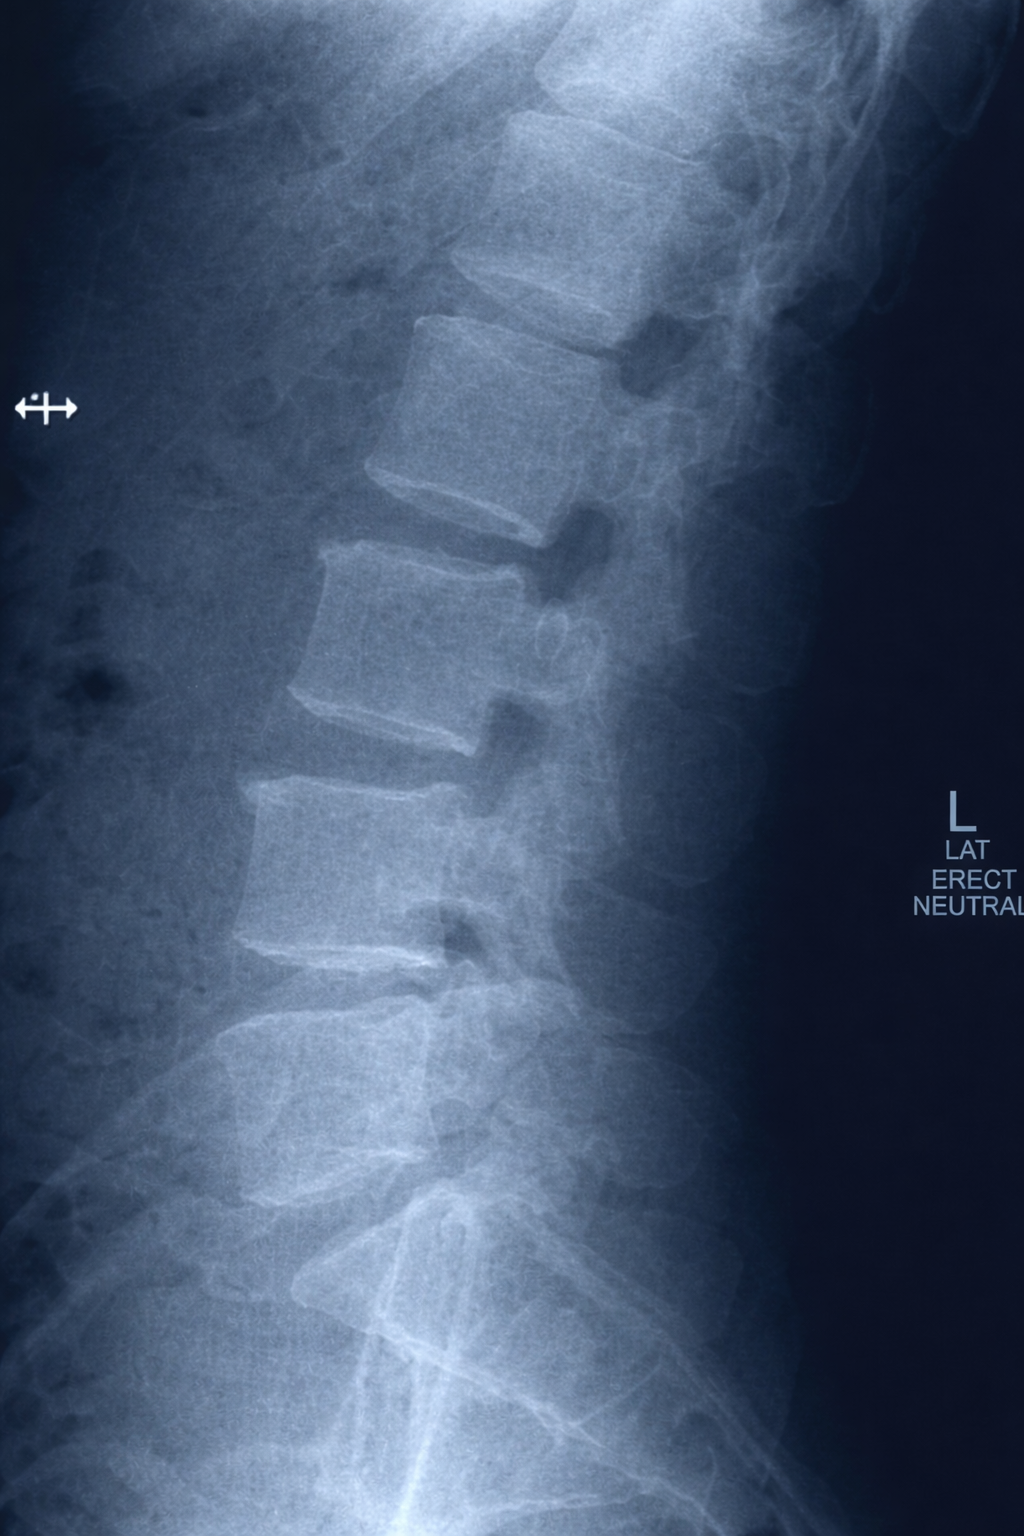

Spinal Instability & Symptomatic Disk, Joints and Ligaments

Platform identifies imaging findings related to spinal instability, symptomatic disc abnormalities, facet joint changes, and ligamentous injuries for physician review and clinical correlation.

AI-Driven Clinical Insight

Multi-Level Spine Analysis Example

Imaging shows findings consistent with instability at L4/5 and L5/S1 following prior percutaneous disc procedure. Board-certified physician review recommended for treatment planning.